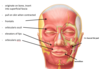

what is the lymphatic drainage of the lateral surface of the superior half of the auricle

parotid lymph nodes

what is the lymphatic drainage of the cranial surface of the superior half of the auricle

mastoid lymph nodes (purple) and deep cervical (light green)

what is the lymphatic drainage of the rest of the auricle, including the lobe

superficial cervical lymph nodes (dark green)

where does all lymph from the auricle eventually drain to

deep cervical lymph nodes (in carotid sheath), thoracic duct and then venous angle